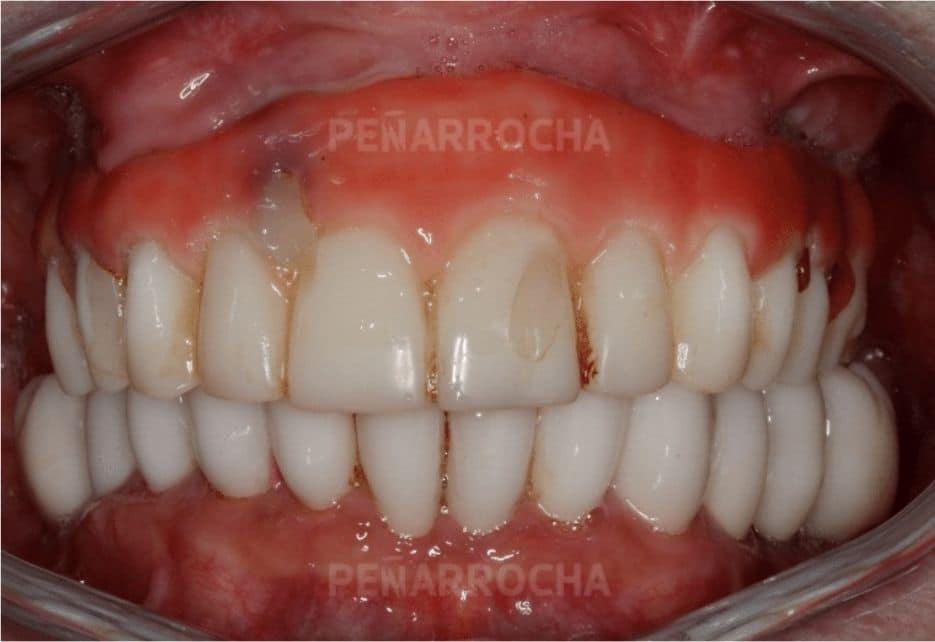

Casos de éxito de implantes dentales con poco hueso en IDIM

En IDIM, contamos con más de 35 años de experiencia tratando casos complejos de implantología dental. A lo largo de nuestra trayectoria hemos logrado recuperar sonrisas de pacientes con condiciones óseas muy complicadas, incluida la falta de hueso suficiente para la colocación de implantes dentales.

Sabemos que la falta de hueso puede ser una preocupación importante, pero gracias a las técnicas avanzadas que utilizamos y a nuestro equipo especializado, hemos logrado devolver a nuestros pacientes no solo una sonrisa estética, sino también una funcionalidad óptima en su boca. Cada paciente es único, y por eso, nos centramos en ofrecer soluciones personalizadas para sus necesidades específicas, teniendo en cuenta la cantidad y calidad del hueso disponible.

Además, entendemos que antes de someterse a un tratamiento tan importante como los implantes dentales, es importante conocer otros casos de pacientes que hayan tenido experiencias satisfactorias. Por eso, a continuación, te compartimos algunos de nuestros casos de éxito más representativos de implantes dentales en pacientes con poco hueso:

Después: